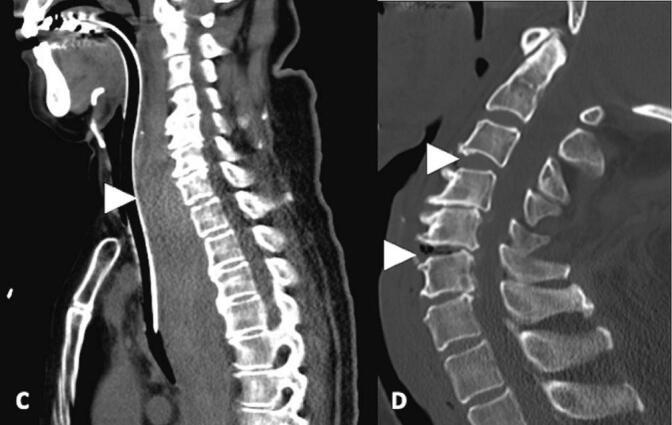

Case 1: A 78-year-old man was transferred to our emergency department due to cardiac arrest. He presented with respiratory insufficiency after a ground level fall. His neck was swollen, and the attending physician performed an emergent cricothyroidotomy to secure his airway and administered intravenous adrenaline. Computed tomography revealed a massive retropharyngeal hematoma and severe hypoxic encephalopathy. Despite a temporary return of spontaneous circulation (ROSC), the patient died on the admission day.Case 2: A 68-year-old woman presented with dyspnea, prompting her family to call an ambulance. On the way to the hospital, the ambulance crew determined the patient was in cardiac arrest. The patient's history revealed a ground level fall in which she hit her face. Computed tomography revealed a massive retropharyngeal hematoma compressing her upper airway. Although ROSC was obtained, the patient died on the 12th day of hospitalization due to hypoxic encephalopathy.Extension views of cervical spine images identified angular instability without cervical bone fracture in both cases, suggesting that possible injuries of the anterior longitudinal ligament contributed to the retropharyngeal hematoma.

Patients presenting with asphyxia after a simple ground level fall accompanied by minor facial injuries should be assessed by emergency physicians for the possibility of a retropharyngeal hematoma. In both cases presented here, unique images indicate possible injuries of the anterior longitudinal ligament.

病例1:一名78岁男性因心脏骤停被转至我院急诊科。他在平地跌倒后出现呼吸功能不全。其颈部肿胀,主治医生紧急行环甲膜切开术以确保气道通畅,并给予静脉注射肾上腺素。计算机断层扫描显示巨大咽后血肿和严重缺氧性脑病。尽管患者暂时恢复了自主循环(ROSC),但于入院当天死亡。病例2:一名68岁女性出现呼吸困难,其家人呼叫了救护车。在送往医院途中,救护人员判定患者心脏骤停。患者病史显示其曾在平地跌倒并撞到面部。计算机断层扫描显示巨大咽后血肿压迫其上气道。尽管恢复了自主循环,但患者因缺氧性脑病于住院第12天死亡。颈椎影像的延伸视图显示两例均存在无颈椎骨折的角状不稳定,提示前纵韧带的可能损伤导致了咽后血肿。

对于在简单平地跌倒并伴有轻微面部损伤后出现窒息的患者,急诊医生应评估其发生咽后血肿的可能性。在本文介绍的两例病例中,独特影像提示前纵韧带可能受损。